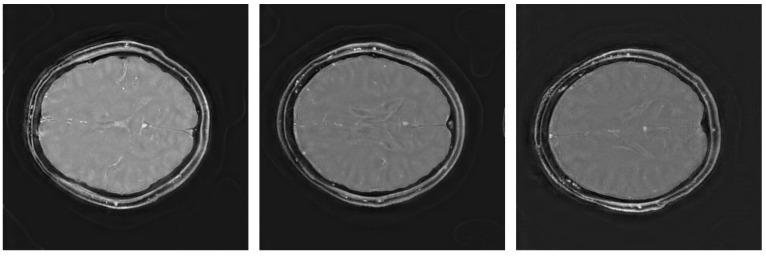

Introduction: An efficient pipeline for rosette trajectory magnetic resonance imaging reconstruction is proposed, combining the inverse Fourier transform with a vision transformer (ViT) network enhanced with a convolutional layer. This method addresses the challenges of reconstructing high-quality images from non-Cartesian data by leveraging the ViT's ability to handle complex spatial dependencies without extensive preprocessing.

Materials and methods: The inverse fast Fourier transform provides a robust initial approximation, which is refined by the ViT network to produce high-fidelity images.

Results and discussion: This approach outperforms established deep learning techniques for normalized root mean squared error, peak signal-to-noise ratio, and entropy-based image quality scores; offers better runtime performance; and remains competitive with respect to other metrics.